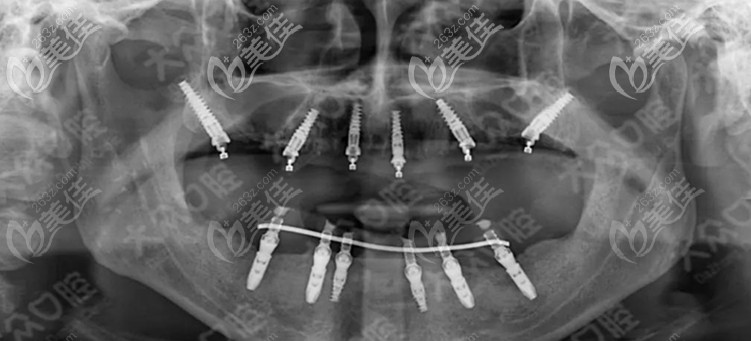

醫(yī)生介紹:周先略,現(xiàn)任武漢愛尚大眾口腔醫(yī)療副總,享受國務(wù)院津貼,從事口腔全科臨床、科研工作40余年,發(fā)表專業(yè)論文50余篇。周先略,出生于1952年8月,于1978年畢業(yè)于湖北口腔醫(yī)學(xué)系,同年被分配到荊州口腔科,工作到現(xiàn)在。擅長(zhǎng)項(xiàng)目:口腔種植、口腔頜面面部畸形、頜面部腫瘤等疾病的治療與診斷,尤其擅長(zhǎng)各類口腔種植中的疑難雜癥。,曾多...